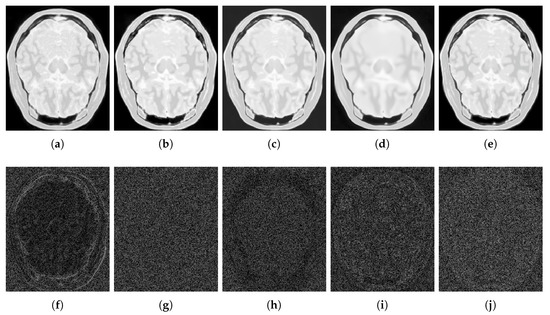

4.2.1. Synthetic Data

4.2.2. Real Data